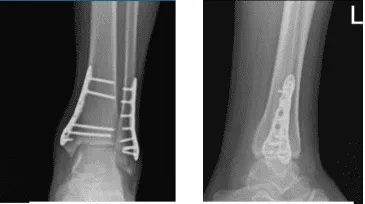

Para entonces, se aconsejó al paciente que realizara la Práctica R.I.C.E (Reposo, Hielo, Compresión y Elevación). Se revisó y monitorizó la radiografía del tobillo izquierdo durante 32 semanas postoperatoria, mostrando fracturas quirúrgicamente tratadas en el peroné distal y la maléola medial.

Radiografía del tobillo izquierdo completada 3 o más visitas 1 semana después de la operación

Radiografía del tobillo izquierdo completada 3 o más visitas-4 semanas después de la operación

Radiografía del tobillo izquierdo completada 3 o más visitas 8 semanas después de la operación

Radiografía del tobillo izquierdo completada 3 o más visitas a las 16 semanas postoperatorias

Radiografía del tobillo izquierdo completada 3 o más visitas 8 meses después de la operación